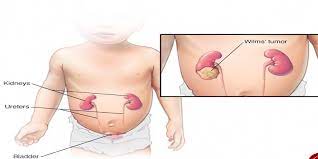

قیمت: 78٬000 تومان - دسته بندی فایل: علوم پزشکیپاورپوینت نفروبلاستوما

فروش ویژه پاورپوینت حرفه ای نفروبلاستوما با تخفیف استثنایی فقط 134000 هزار تومان تعداد اسلاید : 87 اسلاید